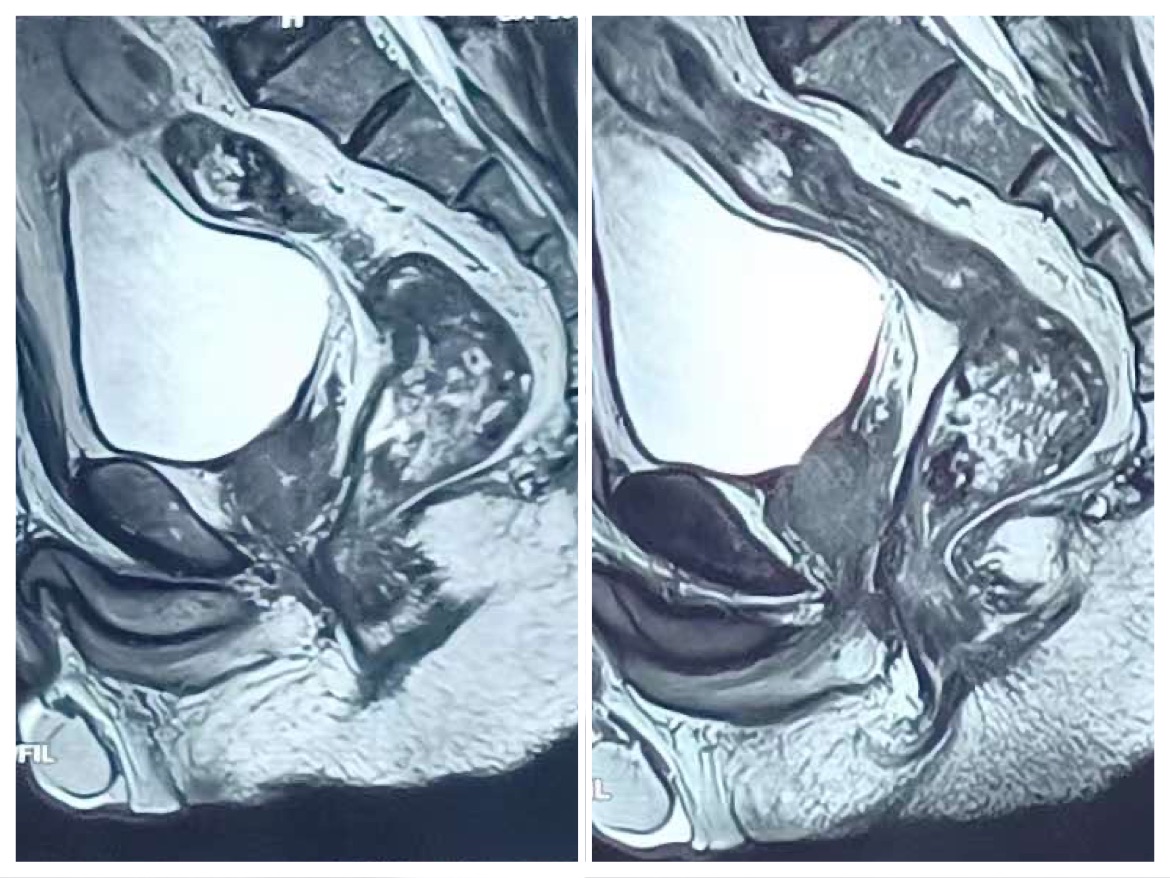

患者3年前因尿频、尿急排尿困难就诊于外院,考虑为前列腺癌,行前列腺穿刺活检,确诊为前列腺癌,格林森评分4+5=9分,未行手术,经不规律内分泌治疗3年,近日尿频尿急排尿困难症状反复来诊,经我院泌尿外科重新评估患者病情:前列腺核磁共振及骨扫描提示:未见转移及浸润,仍有手术指征,向患者家属反复沟通后,决定行经腹膜外途径前列腺癌根治性切除手术。

4、影像学检查,比如B超、磁共振,通过检查看看有没有前列腺的可疑结节,肿块性病灶,尤其是外周带肿块性占位,肿瘤的可能性就会大大增加。